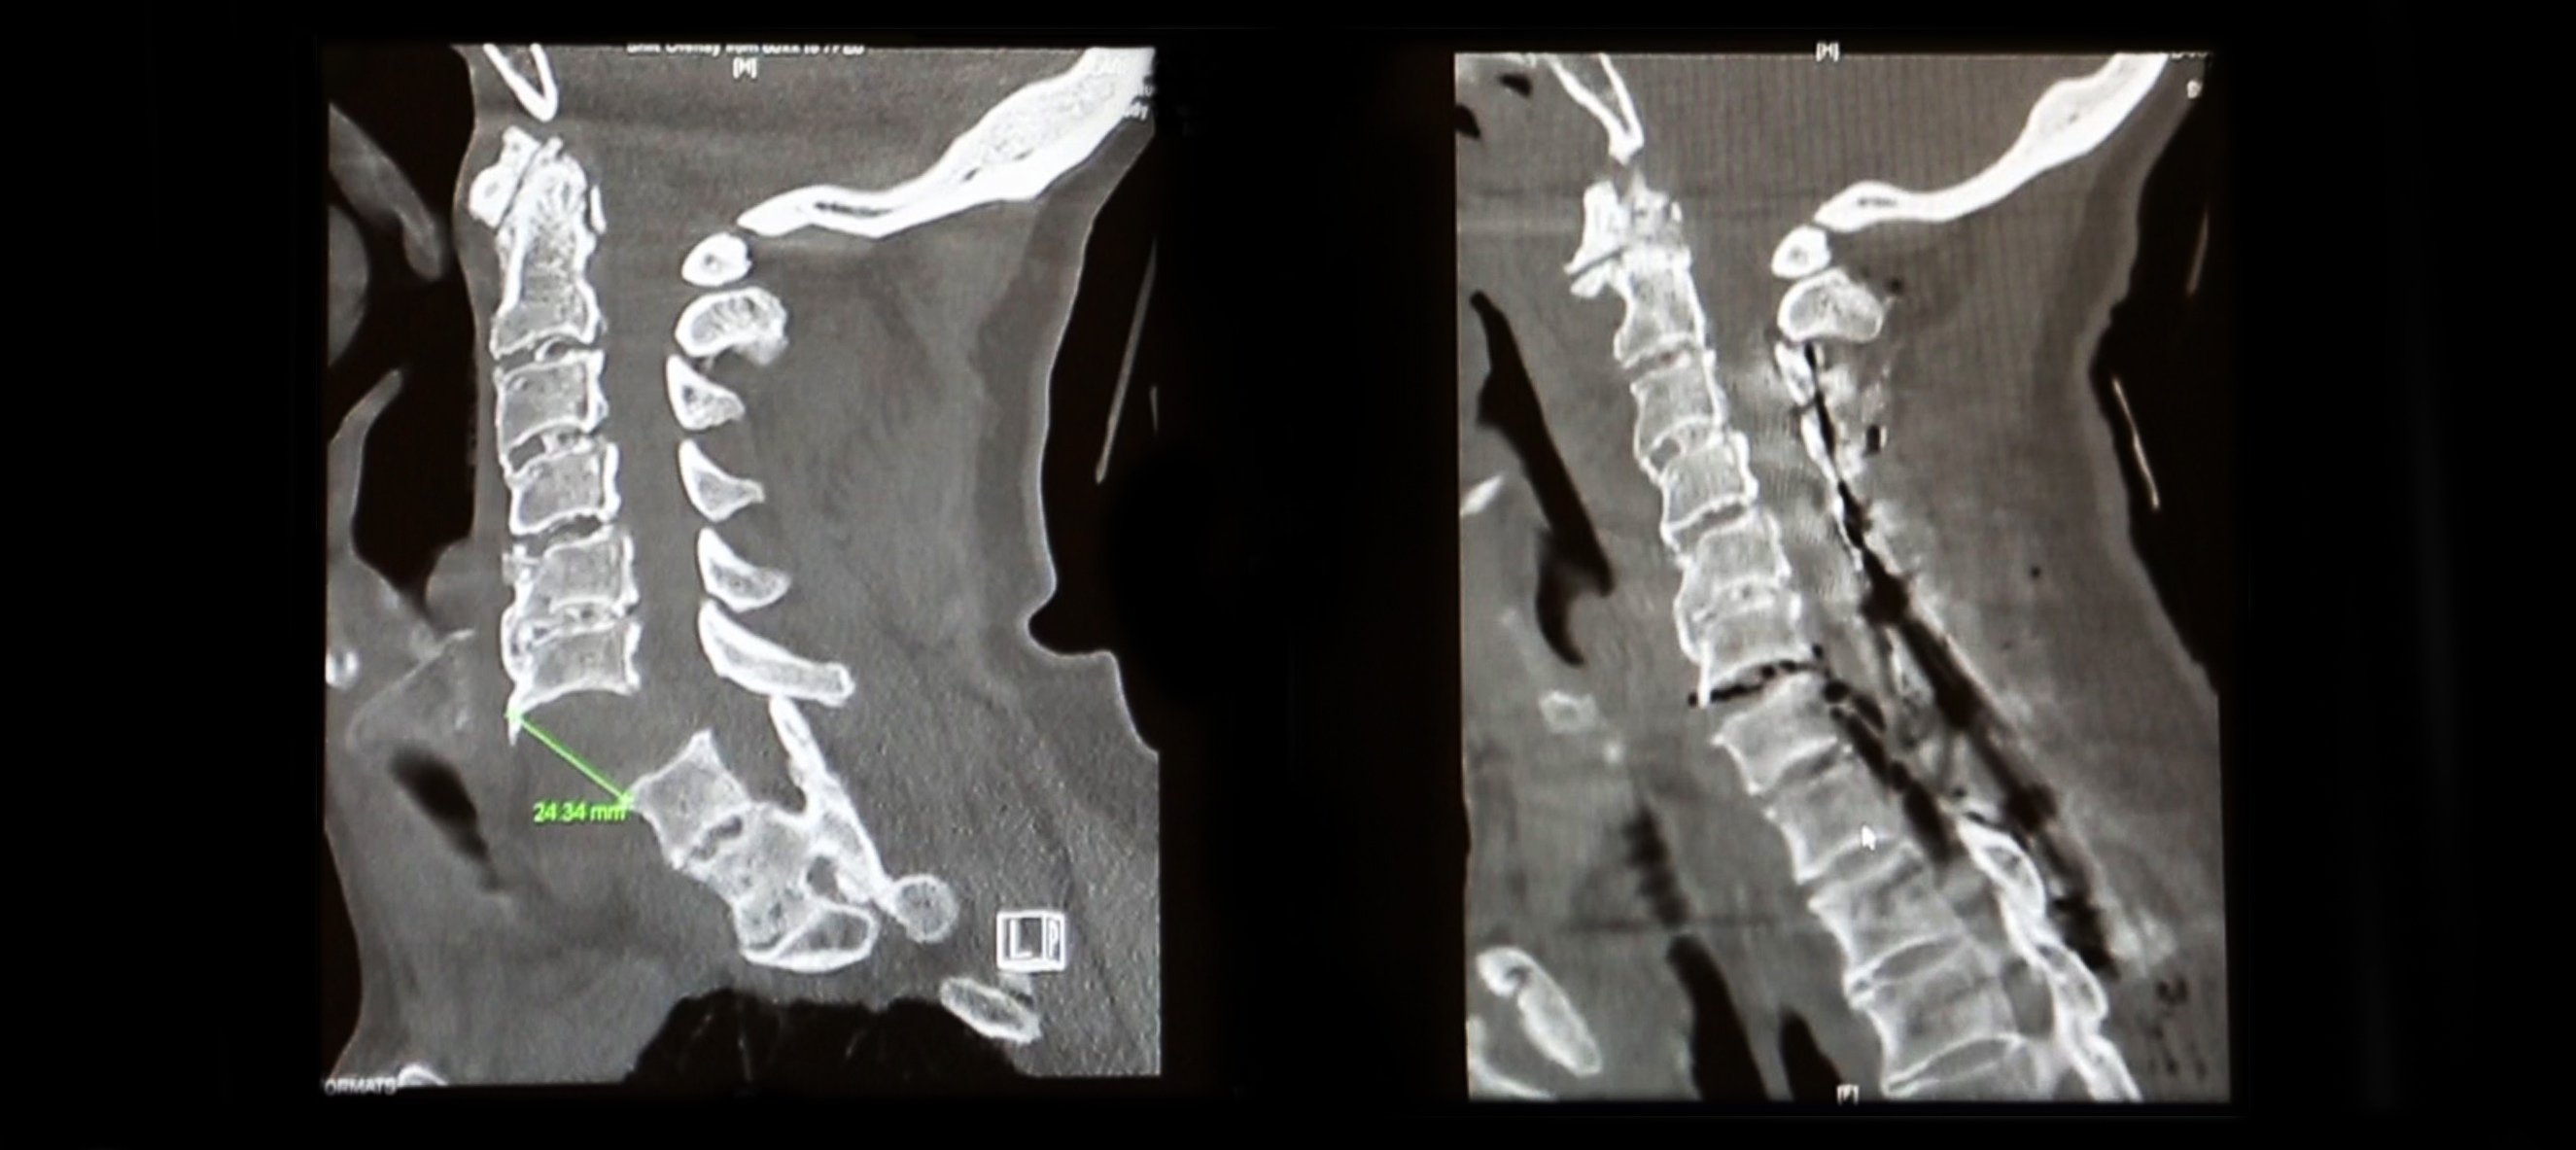

James Clark's spinal column before and after surgery to repair the severed portion

James Clark's spinal column before and after surgery

Dr. Goodwin used X-ray guidance to put Mr. Clark’s spine back into alignment and insert screws that would hold it in place in order for his body to heal.